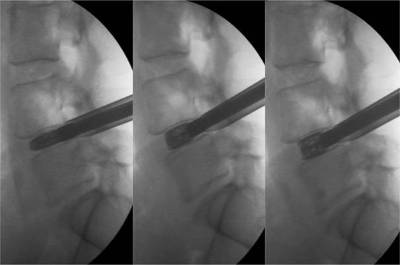

Fluoroscopic image of the placement and expansion of an expandable cage in a collapsed intervertebral disc. From left to right note the progressive expansion of the cage and the restoration of the intervertebral disc’s height